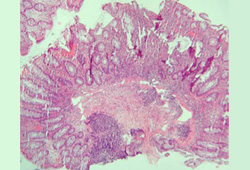

biópsia tecidual

Biópsias segmentares do cólon e do íleo devem ser obtidas para avaliar a evidência microscópica de doença de Crohn (DC).[70] As características microscópicas que ajudam a distinguir a colite ulcerativa da DC incluem granulomas, a alteração da arquitetura e a distribuição da doença.[81] A inflamação granulomatosa é, entretanto, relatada em uma minoria de pacientes com DC (30% a 50%); ela não é necessária para o diagnóstico.[71][81][Figure caption and citation for the preceding image starts]: Inflamação significativa na parede do cólon, alargamento da submucosa e agregados linfoides densos na submucosaFornecido pelo Dr. Wissam Bleibel, Dr. Bishal Mainali, Dr. Chandrashekhar Thukral e Dr. Mark A. Peppercorn, os autores anteriores deste tópico [Citation ends].

[Figure caption and citation for the preceding image starts]: Granulomas em um paciente com doença de Crohn; observe o agregado de histiócitos epitelioidesFornecido pelo Dr. Wissam Bleibel, Dr. Bishal Mainali, Dr. Chandrashekhar Thukral e Dr. Mark A. Peppercorn, os autores anteriores deste tópico [Citation ends].

[Figure caption and citation for the preceding image starts]: Criptite e abscessos em cripta com distorção morfológica das criptas acompanhadas de inflamação e plasmócitos e linfócitos abundantesFornecido pelo Dr. Wissam Bleibel, Dr. Bishal Mainali, Dr. Chandrashekhar Thukral e Dr. Mark A. Peppercorn, os autores anteriores deste tópico [Citation ends].

Biópsias de mucosa não comprometida ajudam a identificar a extensão da doença histológica.[71] Se tuberculose estiver sendo cogitada, o tecido das biópsias ileocecais poderá ser testado quanto à presença de Mycobacterium tuberculosis.[69]

Resultado

biópsias da mucosa do intestino demonstram o envolvimento transmural com granulomas não caseosos